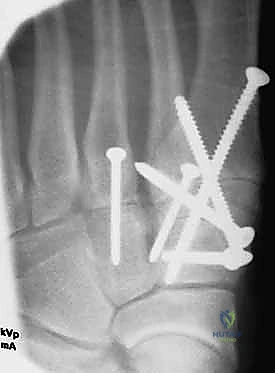

1. الرد المفتوح والتثبيت الداخلي (ORIF - Open Reduction and Internal Fixation)

هذا هو الإجراء الكلاسيكي والأكثر شيوعاً. يهدف إلى إعادة العظام إلى مكانها الطبيعي (الرد) وتثبيتها باستخدام معدات طبية (مسامير، شرائح، أو أسلاك) حتى تلتئم الأربطة والعظام.

خطوات العملية:

1. التخدير: يتم إجراء الجراحة تحت التخدير الموضعي (النصفي) أو العام.

2. الشق الجراحي: يقوم الدكتور هطيف بعمل شق جراحي دقيق (أو شقين) على ظهر القدم للوصول إلى المفاصل المصابة، مع الحرص الشديد على حماية الأعصاب والأوعية الدموية الدقيقة في تلك المنطقة باستخدام مبادئ الجراحة المجهرية.

3. التنظيف والرد: يتم تنظيف المفاصل من أي شظايا عظمية أو أنسجة محشورة تمنع عودة العظام لمكانها. ثم يتم إعادة العظام بحذر شديد إلى محاذاتها التشريحية الدقيقة (القوس الروماني).

4. التثبيت (Fixation): يتم تثبيت العظام باستخدام مسامير معدنية خاصة (Solid or Cannulated Screws) تعبر المفاصل لتثبيتها بإحكام. في بعض الحالات، يتم استخدام شرائح معدنية صغيرة للحفاظ على الاستقرار.

5. مسمار ليزفرانك: الخطوة الأهم هي وضع "مسمار ليزفرانك" (Lisfranc Screw) الذي يمر من العظم المسماري الإنسي إلى قاعدة المشط الثاني، لتعويض وظيفة الرباط الممزق.

6. الإغلاق: يتم إغلاق الشقوق الجراحية بعناية تجميلية ووضع القدم في جبيرة لحمايتها.